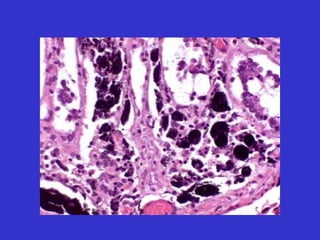

Biopsia y citologia